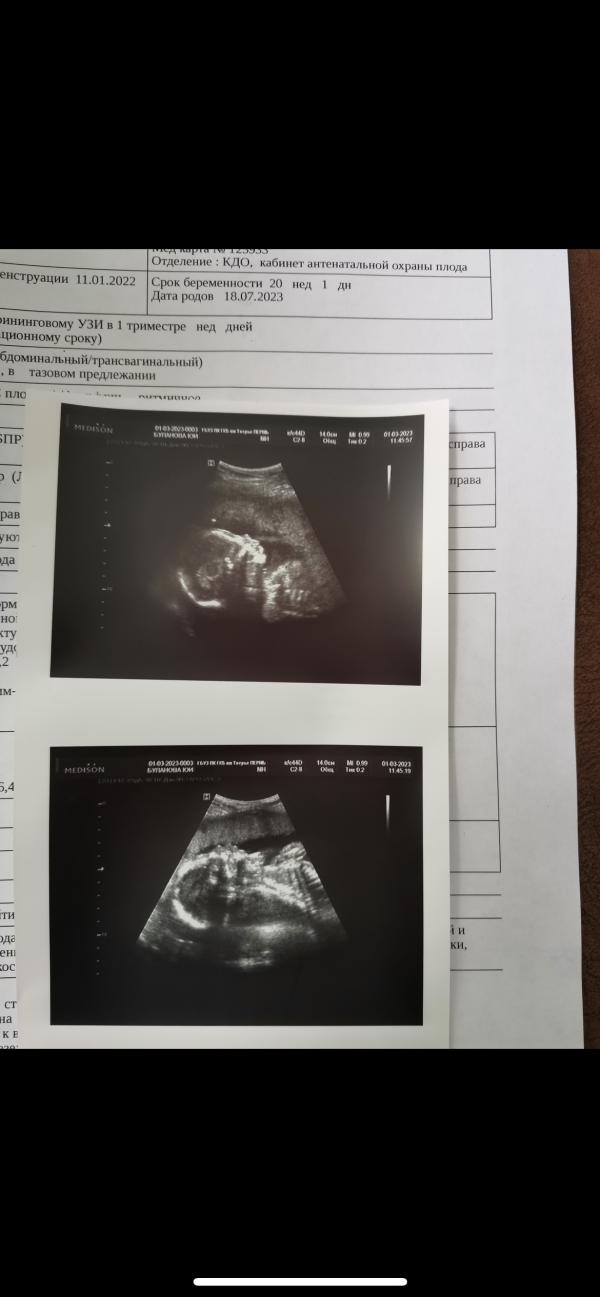

Оставлю здесь❤️прошла все скрининги😇

3 скрининг сделали в самой консультации?